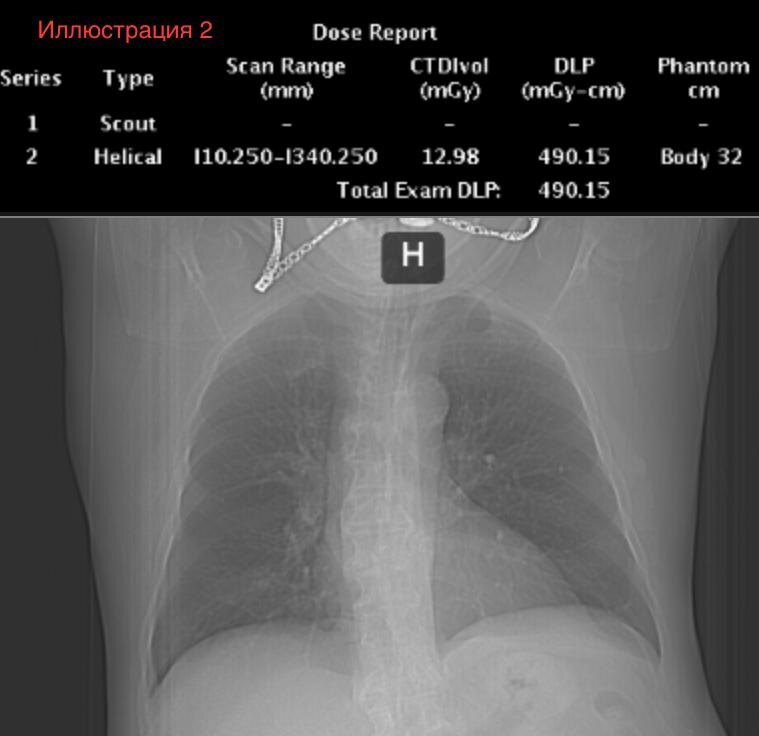

1. Сверху будет Dose Report . У этих DR есть одно новое поле «Scan range» - это протяженность сканирования. Самое главное, на что мы должны обратить внимание - это DLP. Но обращайте внимание и на протяженность сканирования - это важно! Как определить протяженность сканирования - я укажу ее в каждом кейсе, а как её определить исходя из DR - это будет задание для вас!

2. Снизу будет фронтальная топограмма - глядя на нее, вы можете примерно оценить комплекцию пациента.

Исследования выполнены в одном и том же ЛПУ на одном и том же аппарате и на одинаковых протоколах сканирования.

Ваша задача: оценить, насколько сильно меняется DLP у разных пациентов и сделать предположения , почему DLP меняется.

Иллюстрация 2. КТ ОГК. Длина сканирования 330 мм. DLP 490,15 Эффективная доза 8,3 мЗв.

Вывод №1. На иллюстрации 1 довольно худой пациент, а у пациента на иллюстрации 2 подкожная клетчатка выражена избыточно, что видно по топограммам. По цифрам мы видим, что DLP у худого и полного пациентов могут отличаться в три раза! Это значит, что масса тела имеет прямое влияние на дозу. В моей практике я встречал пятикратную разницу, если сравнивать истощенных пациентов с кахексией и пациентов с ожирением четвертой степени!